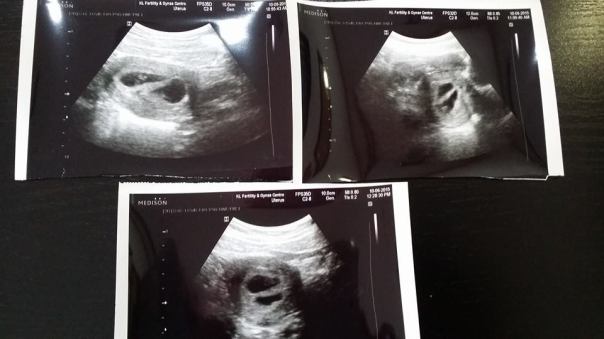

Mungkin bersempena hari jadi twins Dr Tasha ie ‘twins mode’ – Terdapat 5 pasangan yang Dr Tasha scan hari ini di klinik disahkan hamil dengan kembar selepas rawatan kesuburan mereka. Di KL Fertility Centre adalah menjadi lazim hanya maksimum 2 embrio sahaja akan dipindahkan semasa proses Embryo transfer. Ini adalah salah satu langkah yang kami ambil untuk mengurangkan risiko untuk hamil kembar. Akan tetapi, sekurang-kurangnya 20% wanita hamil akan hamil kembar dua apabila 2 embrio dipindahkan sekaligus.